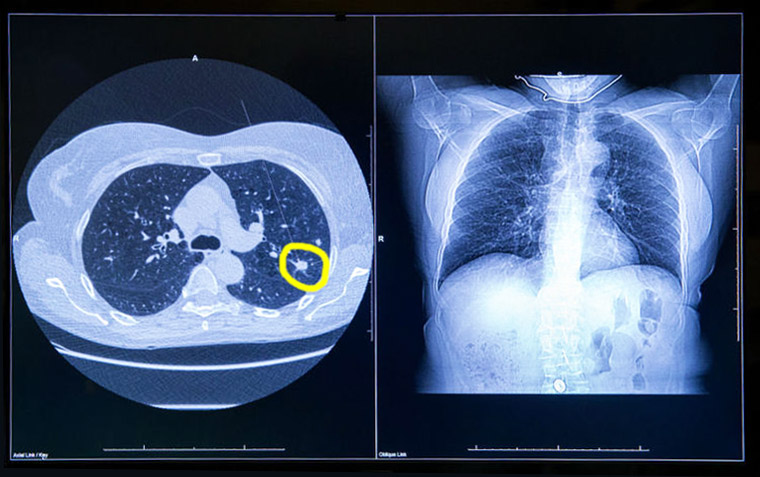

Pembrolizumab neoadyuvante más quimioterapia seguida de pembrolizumab adyuvante vs quimioterapia neoadyuvante sola para el cáncer de pulmón no microcítico en etapa temprana

16 septiembre 2024

El beneficio de supervivencia general con pembrolizumab neoadyuvante más quimioterapia seguido de pembrolizumab adyuvante, en comparación con la quimioterapia neoadyuvante sola, junto con un perfil de seguridad manejable, respaldan el uso de pembrolizumab perioperatorio en pacientes con cáncer de pulmón no microcítico resecable en estadio temprano. The Lancet, 14 de septiembre de 2024.